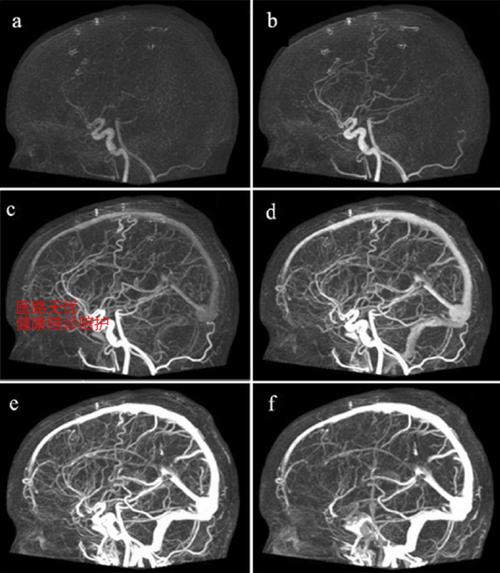

头颈部CTA:

(图片来源网络,侵删)- AI应用: 自动筛查脑动脉瘤、动脉瘤夹层,评估 Willis环的完整性,识别颈动脉狭窄和斑块特征,在急性卒中流程中,AI能快速判断大血管闭塞。